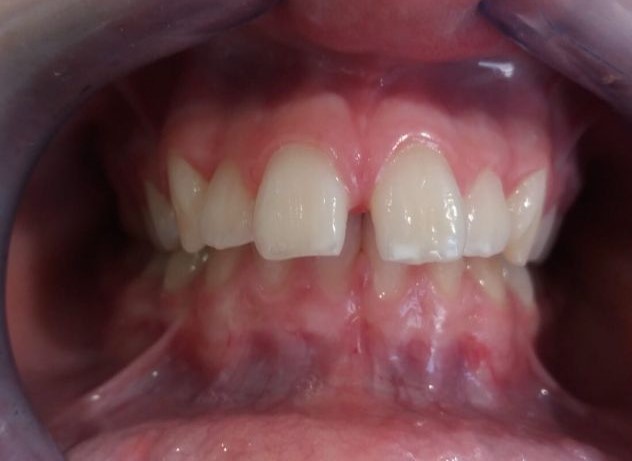

Vamos a ver el tratamiento de ortodoncia de un paciente de 11 años de edad en el que se observa una clase II de tipo dento-alveolar. Tiene un perfil de ligera protrusión del maxilar superior y retrusión de la mandíbula. Los incisivos inferiores llegan a contactar con el paladar superior pero muy hacia atrás. Esto le da un perfil de pájaro. Siendo la causa diversa en las que se mezcla diferentes parafunciones como interposición del labio inferior entre los dientes incisivos superiores e inferiores, o también interposición lingual al tragar etc. Es decir son los músculos (labio, lengua etc.) con sus malos hábitos los que producen las mal oclusiones e incluso trastornos del desarrollo óseo maxilomandibular normal. Es decir los músculos de la cara son los arquitectos de los huesos faciales, en este caso que exponemos para mal.

Recordamos que los músculos de la cara son los arquitectos de los huesos faciales, en este caso el aparato funcional, que es como un músculo, actúa para bien. Trascurrido este tiempo el paciente lleva elásticos de cierre para cerrar espacios dentales y resto de ajustes oclusales. Posteriormente a la retirada del aparato de ortodoncia el paciente lleva retenciones fijas y removibles durante la noche que garanticen el resultado en cuanto a recidivas.